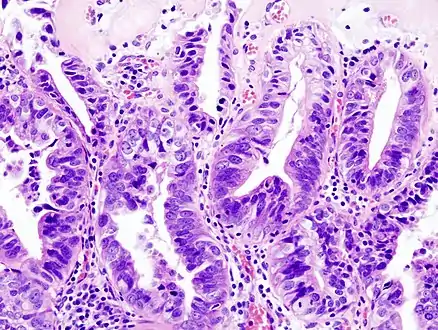

Most tumors are adenocarcinomas, with a small percent being squamous cell carcinomas.